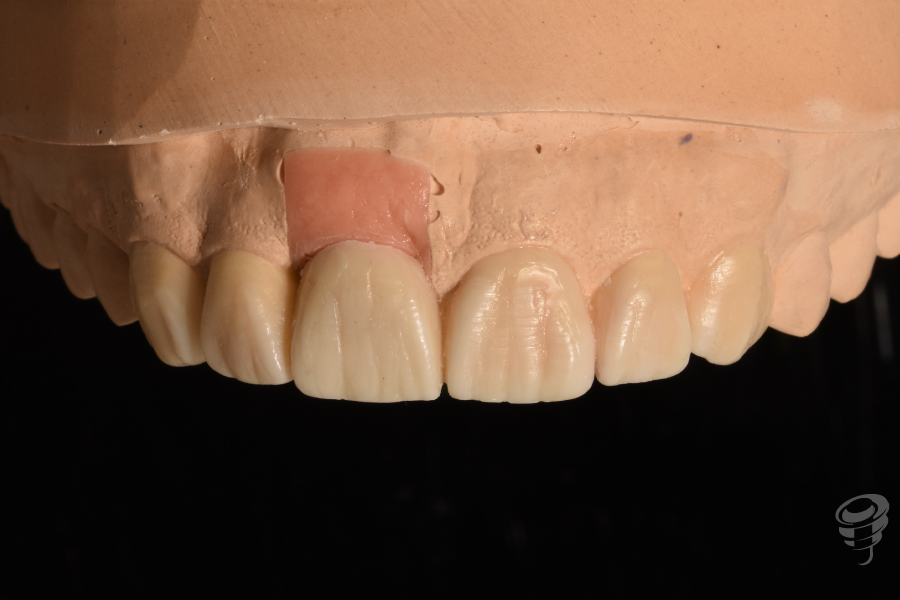

- Impresión convencional para realizar un encerado diagnóstico estético y posteriormente una realización de réplica del perfil de emergencia con la técnica de Hinds, para solapar una medida convencional con una digital (escáner intraoral).

Figura 30

Figura 31

Figura 32

Figura 33

Figura 34

Figura 35

Figura 36

Figura 37

Figura 38

Figura 39